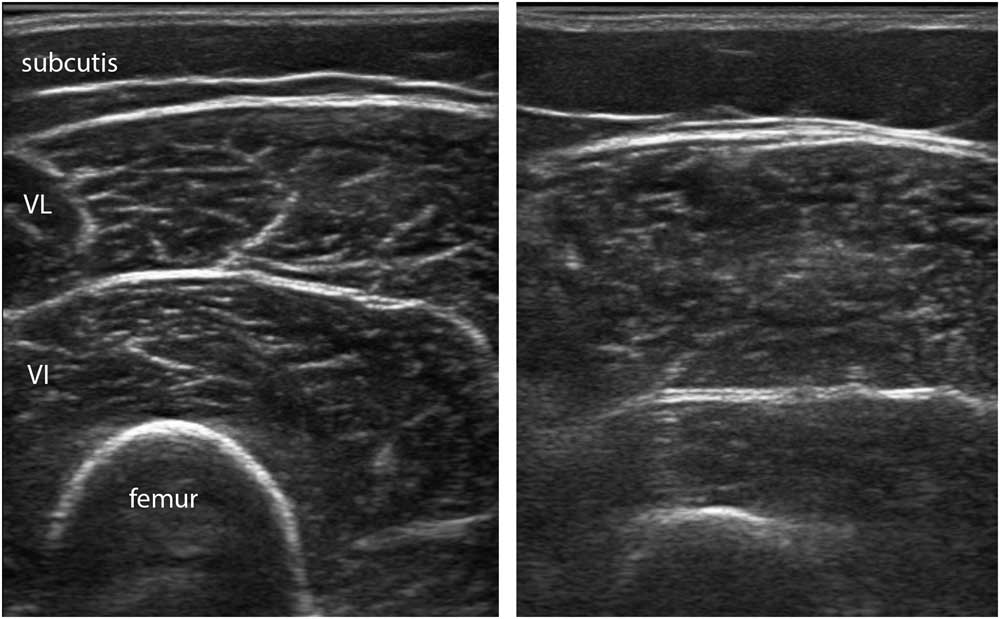

Visual muscle evaluation and grading are both dependent on operator experience. All healthy muscles look slightly different on ultrasound because of differences in architecture and connective tissue content (see e.g., Figures 1, 7A, 11A, 11B). In addition, their echogenicity also strongly depends on age and the fat content of muscle. People aged 40-50 years and over or obese people will have whiter muscles (Figure 14).Reference Arts, Pillen, Schelhaas, Overeem and Zwarts 25 , Reference Nijboer-Oosterveld, van Alfen and Pillen 26 The appearance of normal and diseased muscle will also vary considerably from one ultrasound machine and preset to another, so that using a machine different from the one the examiner is used to will make it much more difficult to assess images correctly (see Figure 5).

Figure 14 This panel shows the vastus lateralis muscle in two healthy female subjects, one with a body mass index (BMI) of 18.7 (left image) and one with a BMI of 30.1 (right image). The muscle on the right has more intramuscular fat depositions, leading to a more grainy and somewhat fuzzy appearance of the intramuscular fascia.